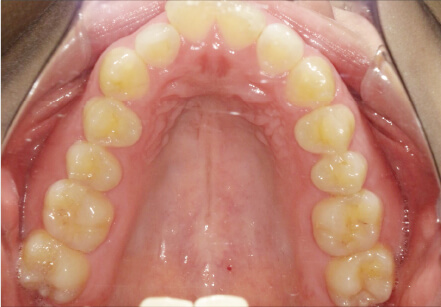

叢生の症例

41歳

/

女性

相談内容

正中がズレている。傾いている歯がある。

カウンセリング・診断結果

叢生・アレルギーなし・ext、IPR、アタッチメント、ミニスクリュー、ゴム掛け承諾

治療内容・方法

全額アライナー矯正・左下7セラミックはそのまま進めていく

術後の経過・現在の様子

クリアライナー使用

治療のリスク

痛み・歯根吸収・歯肉退縮・虫歯・後戻り

費用・治療期間

880,000円、1年9ヶ月

トレーニングなど